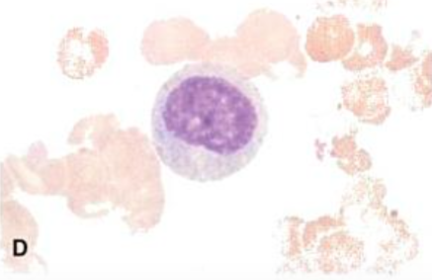

Fuente: Rodak, E. (2004). Hematología: Fundamentos y Aplicaciones. (2da ed.). Madrid, España: Editorial Médica Plasmocito Morfológicamente, son más grandes que los linfocitos B independientes del antígeno, son redondos con un citoplasma abundante y gránulos azurófiros, un núcleo periférico ovalado basófilo (Rodak, 2004).

Es el linfocito B completamente maduro y funcional, presenta IgM e IgD en su membrana, en este estado poseen especificidad y son completamente dependientes del antígeno (Rodak, 2004). Fuente: Rodak, E. (2004). Hematología: Fundamentos y Aplicaciones. (2da ed.). Madrid, España: Editorial Médica